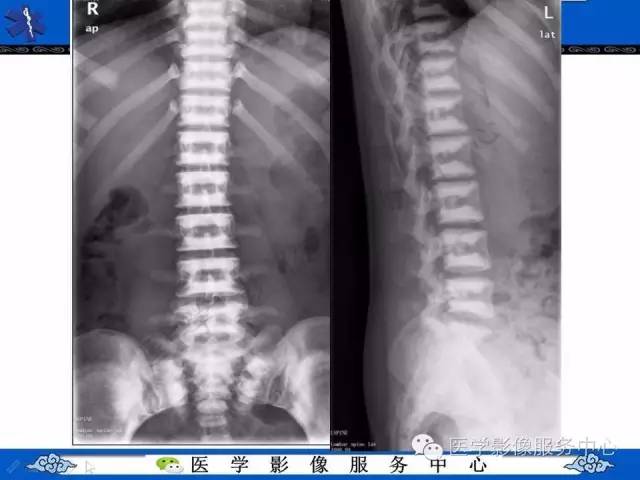

【PPT】石骨症——少见的骨病例,但是过目不忘!